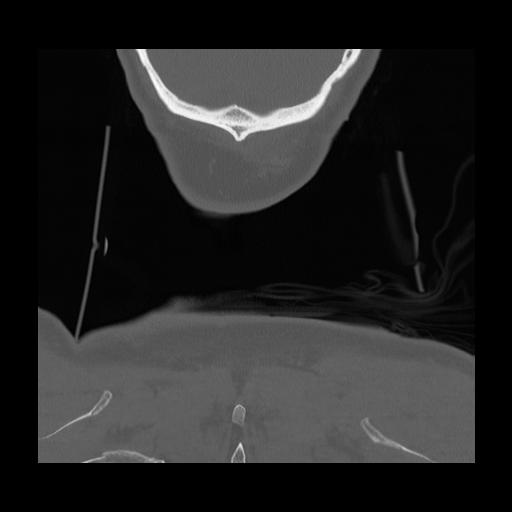

16 HUESO,,Coronal,2.000,HUESO,Coronal,